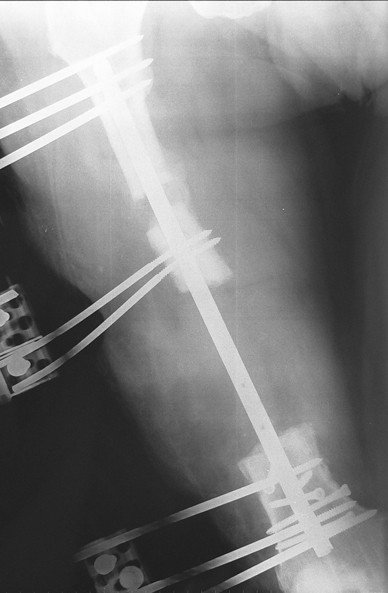

Uygun radikal debridman tüm nekrotik kemik ve yumuşak dokuların çıkartılmasını gerektirir, ve sıklıkla uzuvda instabiliteye neden olur. Kalan kemik ve yumuşak doku defektinin bir şekilde fiksasyonu ve rekonstrüksiyonu gereklidir. İlizarov’un ortaya koyduğu distraksiyon osteogenezi yöntemi, kaynamanın elde edilmesi, deformitenin düzeltilmesi, bacak boy eşitsizliğinin giderilmesi ve segmental defektlerin rekonstrükte edilmesi için başarıyla kullanılmaktadır.

Eksternal fiksatör ile geçen süre (eksternal fiksasyon indeksi), gereken distraksiyon miktarına bağlıdır ve bu süre boyunca bazı komplikasyonlarla karşılaşılabilir. Distraksiyon dönemi sona erdikten sonra, distraksiyon süresinin iki katını aşan konsolidasyon döneminde hastalar eksternal fiksatörü zorlukla tolere edebilirler. Yeterli konsolidasyon sağlanmadan eksternal fiksatör çıkartılırsa ise kırıklar, deformite ve kısalık oluşabilir. Hastanın fiksatör ile birlikte geçirdiği sürenin azaltılması ve böylece hasta konforunun ve aktivite düzeyinin arttırılması için intramedüller çivi üzerinden uzatma yöntemi uygulanmaktadır. Bu yöntemde distraksiyon dönemi sona erdiğinde kemiğin içindeki çivi statik olarak kilitlenmekte ve eksternal fiksatör çıkartılmaktadır. Stabilizasyon intramedüller çivi tarafından sağlandıktan sonra konsolidasyon dönemi gerçekleşmektedir. Bu şekilde hem eksternal fiksatörün uzun süre kalmasından hem de erken çıkartılmasından kaynaklanan komplikasyonların önüne geçilmektedir.